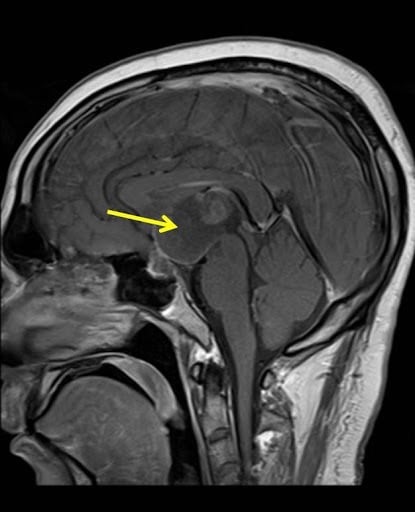

Craniopharyngioma

Targeted clinical protocols for craniopharyngioma, addressing its unique location, low incidence, and complex impact on neuroendocrine function and cognition.

Comprehensive Namtso research solutions for craniopharyngioma, a rare and complex brain tumor.